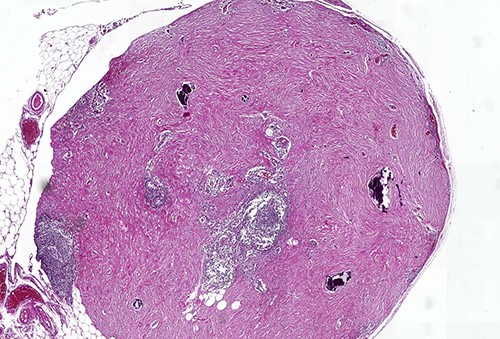

On macroscopic examination, numerous (>100) gray-white-colored grape-like hard nodules were seen, with the largest measuring 4 cm and the smallest measuring 0.2 cm. They were well-circumscribed, unencapsulated, spherical or lobulated and cut surfaces were homogenous, gray-white and firm to rubbery. Microscopically, hypocellular spindle cell proliferations embedded in abundant hyalinized collagen were seen, occasionally dystrophic or psammomatous calcifications interspersed with sparse lymphoplasmacytic infiltrate that may form lymphoid follicles. There was no mitosis, atypia or necrosis (Figs 2 and 3).

Calcifying fibrous tumor with abundant paucicellular hyalinized collagen, interspersed psammomatous or dystrophic calcifications and inflammatory infiltrate consisting of lymphocytes and plasmocytes (H&E, ×4).